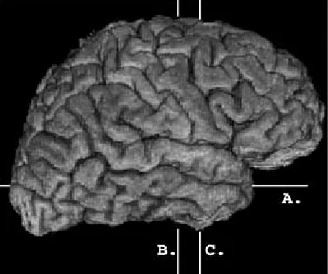

Amerika'nın Kentucky eyaletinde yaşayan bir kadın, beyninin Amigala kısmında yer alan genetik bir bozukluk nedeniyle korku duygusuna sahip değil.

İlk olarak 1994 yılında tıp literatürüne giren bu rahatsızlığın genel ismi Urbach-Wiethe.